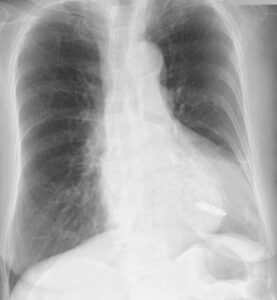

では、もう一つ。下のレントゲンもペースメーカが入っている患者さんのものですが、ペースメーカがどこにあるか分かるでしょうか?

答えは矢印のところです。

これがリードレスペースメーカですが、ペースメーカが植え込まれている情報が無かったり、撮影条件によっては、編集長も見落としそうになることもあります。従来のものと比べた写真が下のものです。